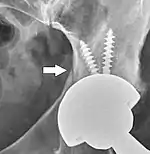

Fracture

Intraoperative fractures may occur. After surgery, bones with internal fixation devices in situ are at risk of periprosthetic fractures at the end of the implant, an area of relative mechanical stress. Post-operative femoral fractures are graded by the Vancouver classification.

On radiography, it is normal to see thin radiolucent areas of less than 2 mm around hip prosthesis components, or between a cement mantle and bone. However, these may still indicate loosening of the prosthesis if they are new or changing, and areas greater than 2 mm may be harmless if they are stable.[21] The most important prognostic factors of cemented cups are absence of radiolucent lines in DeLee and Charnley zone I, as well as adequate cement mantle thickness.[22] In the first year after insertion of uncemented femoral stems, it is normal to have mild subsidence (less than 10 mm).[21] The direct anterior approach has been shown to itself be a risk factor for early femoral component loosening.[23][24][25]